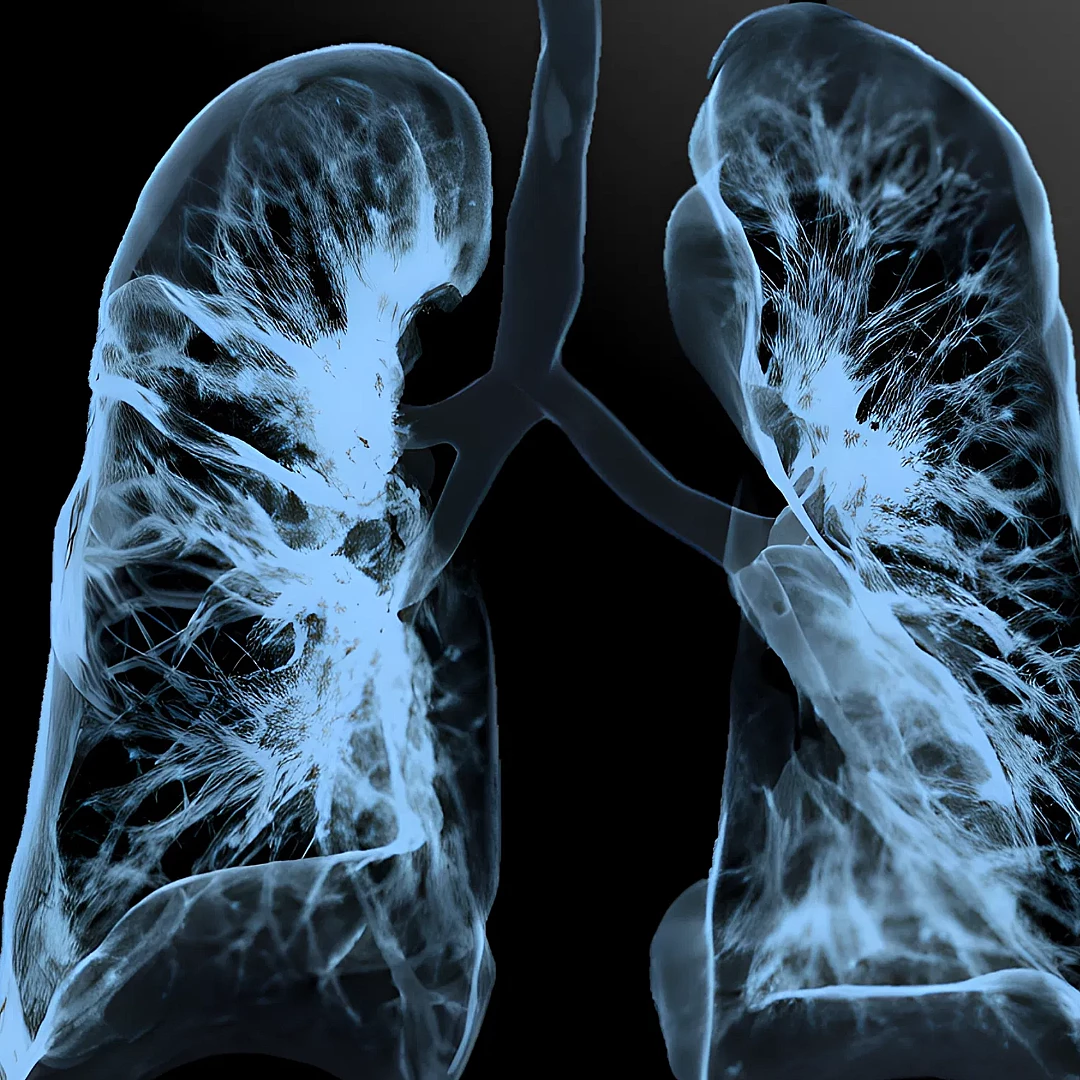

Standard & High-Resolution Chest CT

Standard and High-Resolution Chest CT provides detailed imaging of the lungs, airways, and chest structures to detect infections, tumors, or interstitial lung disease. High-resolution scans offer greater clarity for assessing subtle lung abnormalities with precision.

Pulmonary CT Angiography visualizes the pulmonary arteries to detect blood clots, such as in pulmonary embolism. It’s a fast, contrast-enhanced scan offering accurate diagnosis of lung vascular conditions.

Low-Dose Lung Cancer Screening CT is a quick, low-radiation scan designed to detect early-stage lung cancer in high-risk individuals. It enables early diagnosis, improving treatment outcomes and survival rates.

Virtual Bronchoscopy CT creates a 3D view of the airways using CT data, simulating a real bronchoscopy without inserting a scope. It’s a non-invasive method to detect airway abnormalities, tumors, or obstructions.